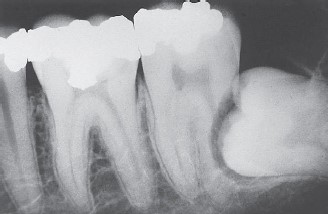

A figura abaixo é um tipo de radiografia odontológica. Assinale a alternativa correta que corresponde a essa radiografia.

Fonte: livro “Fundamentos em Odontologia para TSB e ASB”.